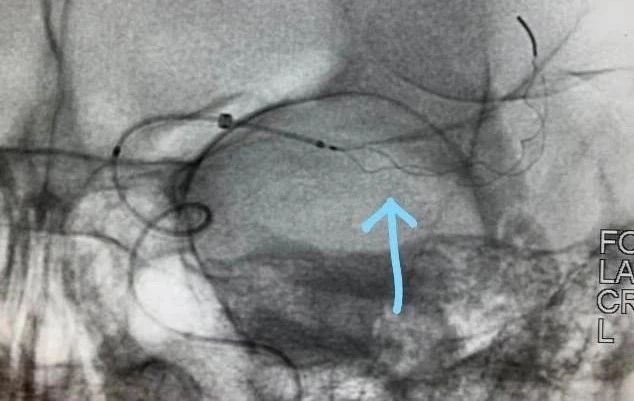

患者发病到入院时间超过4.5h时间,静脉溶栓时间窗超过,考虑大血管病变,患者急诊CT提示左侧大脑中动脉高密度征,ASPECTS评分9分,未见明显低密度灶,结合患者急诊查体,高度提示左侧颈内动脉系统大动脉闭塞。与家属沟通后,急诊行DSA,必要时予血管内治疗。

通过推拉按摩技术后支架打开好转。

术后造影,mTICI分级III。